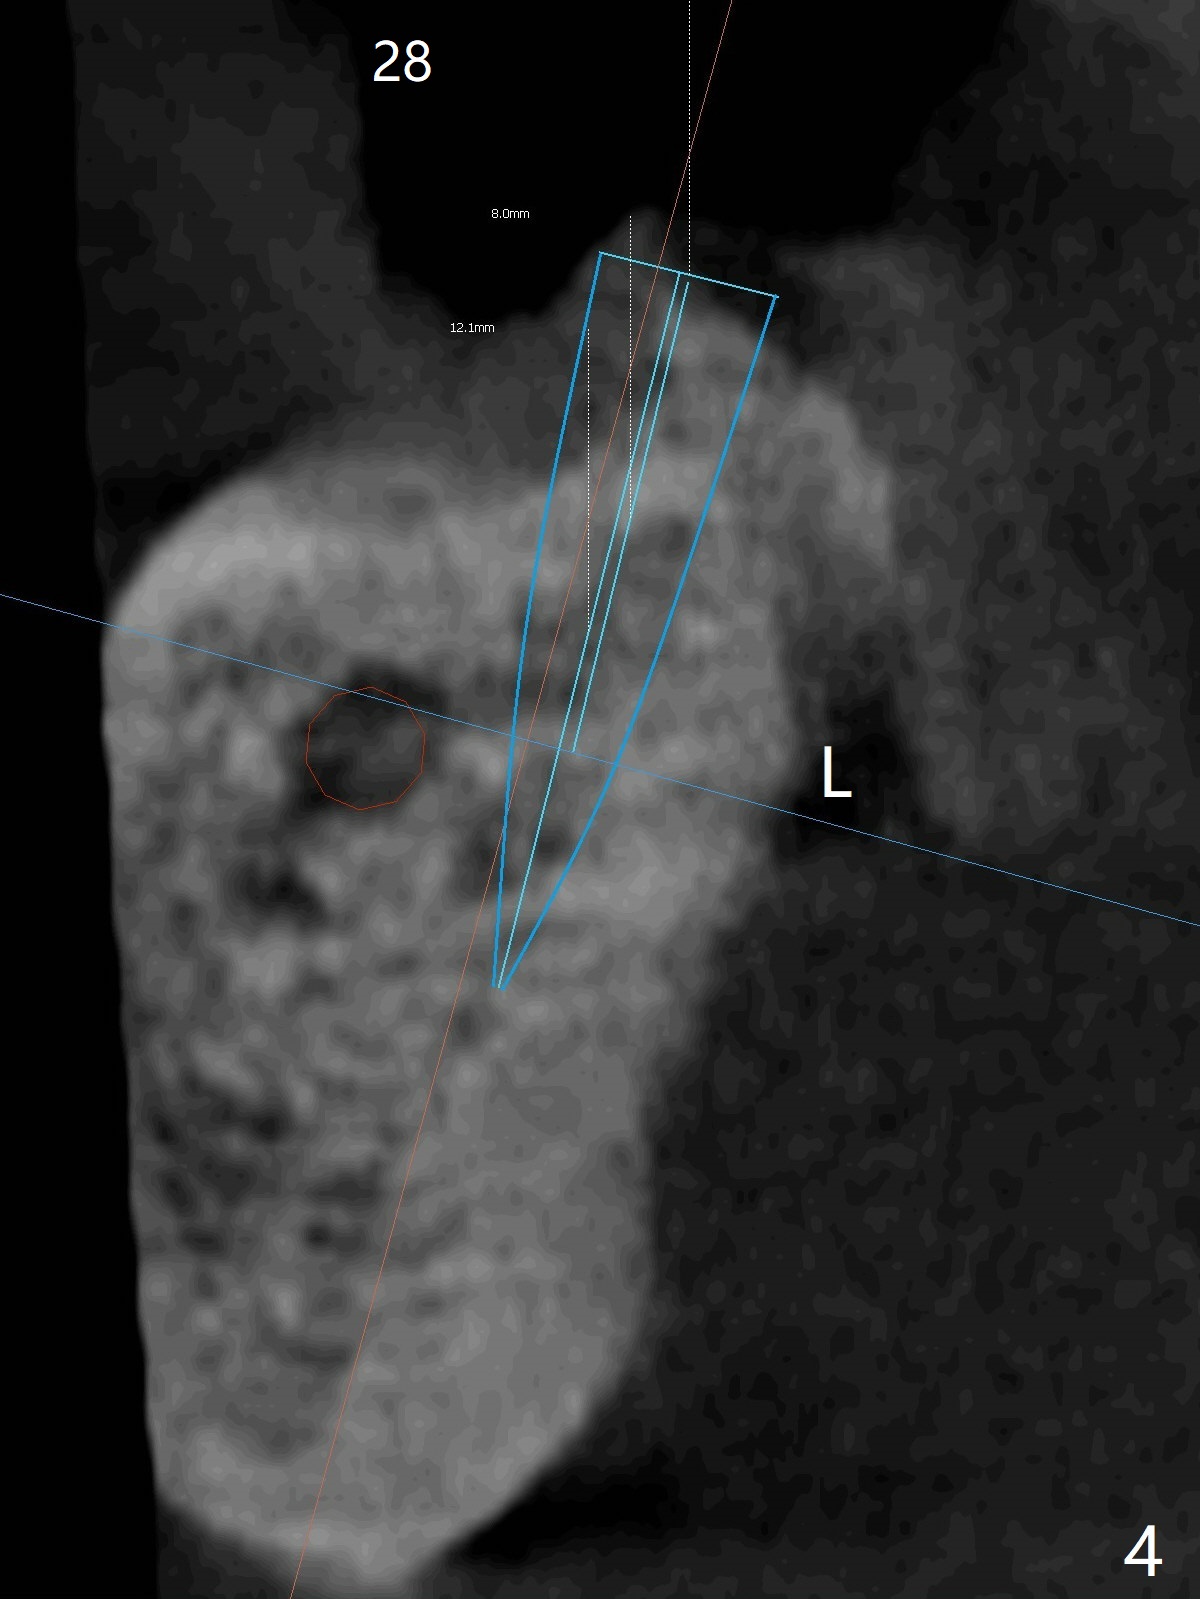

Following placement of a 3 mm 1-piece implant at #26 and two 3.8 mm 2-piece implants with ball abutments at #20 and 21 for a lower edentulous patient, another implant with ball abutment will be placed posterior (approximately at #30, Fig.1,2 (for better spread)) or anterior (approximately at #28, Fig.3,4). The implant will be placed buccal (Fig.2) or lingual (Fig.4) to the Inferior Alveolar Canal or Incisive Canal (safer). Or an implant can be placed at #27, in which there have been 2 implant failures. The last implant was removed 3 months 20 days earlier. Make an incision, study whether the site of #27 has healed with solid bone. If an implant has to be placed at #28, dissect the Mental Nerve first. When stability is low, bury the implant.